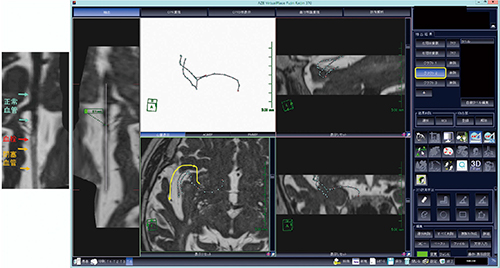

次いで,グラフト2を選択して分岐部から閉塞した血管を追跡し,閉塞血管内の血栓の位置の確認や,血管外径の計測が可能であった(図4)。

図4 中大脳動脈分枝の画像化(2本目)

グラフト2を選択して,中大脳動脈分岐部から閉塞した血管を追跡する。CPR像では閉塞血管内の血栓の位置の確認や,血管外径の計測が可能である。

同様に,グラフト3を選択して中大脳動脈分枝を選択,この血管の血栓の存在を確認できた(図5)。CPR像で血管分岐部の動脈瘤がないことも確認でき,分枝方向や血栓の大きさや長さ,閉塞状況が確認できた。3本の分枝を選択し,血管分枝の立体像の作成までに要した時間は5分以内であり,血栓の存在部位と閉塞血管の位置関係を機械的血栓回収術の術者に伝えることで,血栓回収術の参考画像とすることが可能であった。

図5 中大脳動脈分枝の画像化(3本目)

グラフト3を選択して別の中大脳動脈の血管分枝を追跡し,この血管にも血栓の存在を確認できる。最終的に,3Dの血管分岐のワイヤ像を自由に動かすことで,分岐角度の把握やoperative viewの作成が可能である。